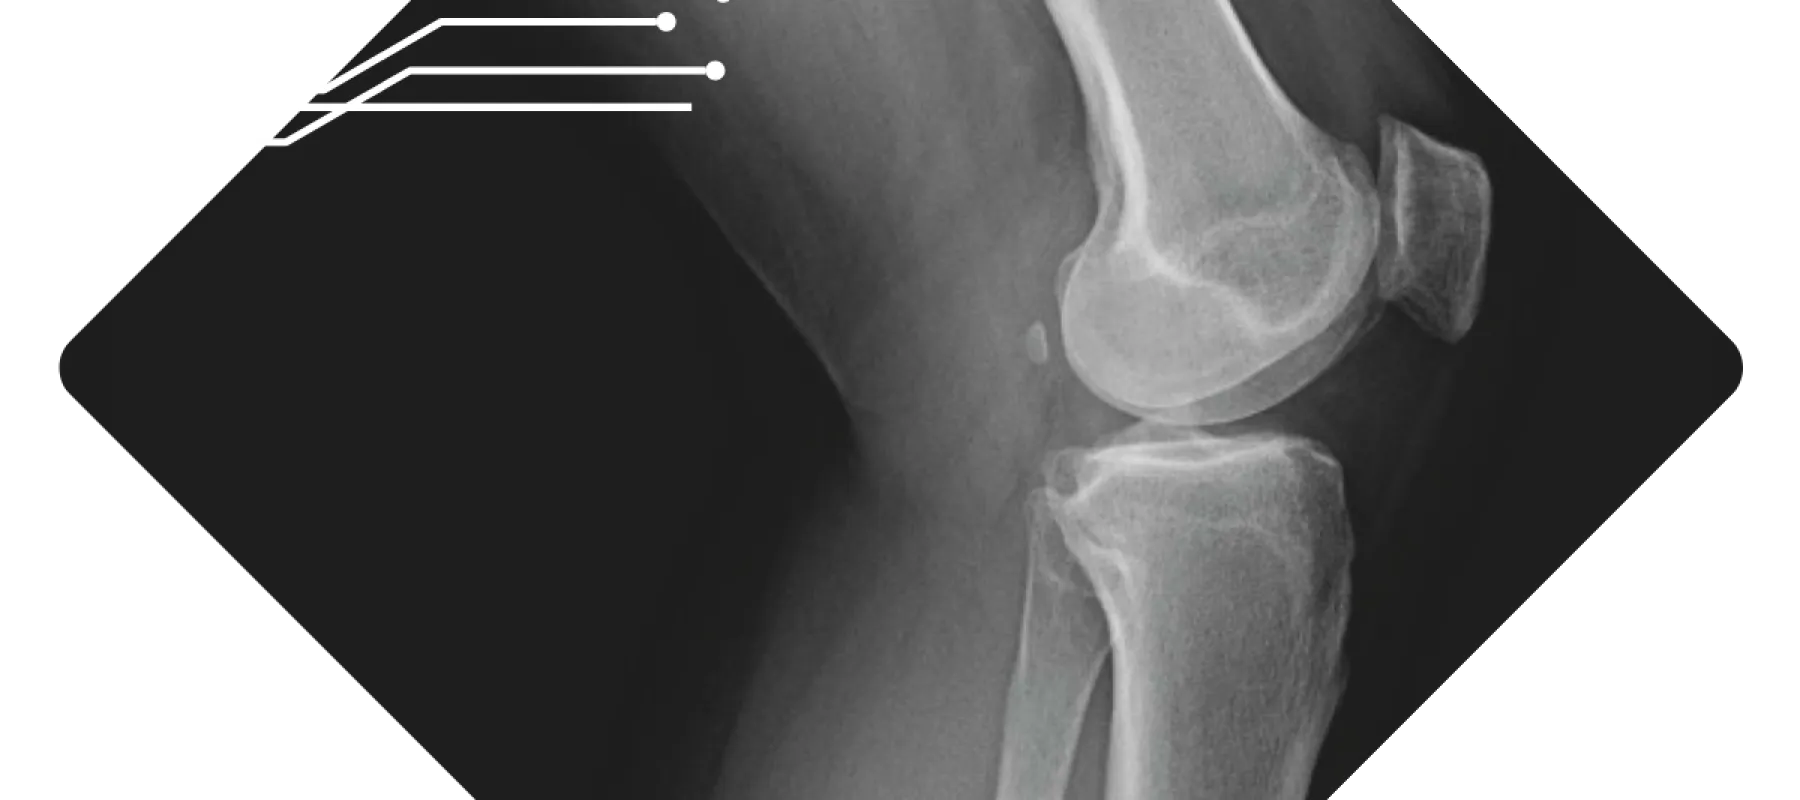

X-ray image showing a human knee joint highlighting bones and joint structure in grayscale.

We believe that the sooner you have answers, the sooner you can heal. Our practice maintains both digital X‑ray and mini‑fluoroscopy machines on‑site, which means we can capture high‑quality images during your appointment without sending you elsewhere. These machines are designed to deliver low‑dose radiation while providing clear, detailed images of bones and joints.

At our practice, your images are reviewed right away so you can talk through the findings and next steps before you head home. In orthopedics across the United States, requesting an X‑ray before your visit is considered standard care. It allows our specialists to see your bones and joints clearly and makes the best use of your time when you come in. We understand some people feel uneasy about imaging, but it's a routine part of musculoskeletal care that's focused on getting you the most accurate evaluation. If you are pregnant or scheduling an appointment for a child, please let us know; we'll coordinate with your doctor and take any extra precautions needed to keep you safe.

At Pacific Crest Orthopedics we have both X-ray and fluoroscopy machines in the office for quick diagnosis and evaluation of all orthopedic injuries. The machines are low radiation and give high-quality images. We can take immediate X-rays of most orthopedic injuries including injuries to the clavicle, shoulder, elbow, wrist, hand, finger, hip, femur, knee, tibia/fibula, ankle, and foot. Each of these can be taken during your appointment and then read promptly by the provider for an efficient diagnosis.

At Pacific Crest Orthopedics, we have advanced X-ray machines right here in our office that use very low radiation to produce clear, detailed images of your bones and joints. We can take X-rays of many areas, including your collarbone, shoulder, elbow, wrist, hand, fingers, hip, thigh, knee, shin, ankle, and foot, all during your appointment. This allows your doctor to quickly review the images and provide an accurate diagnosis so treatment can begin promptly.